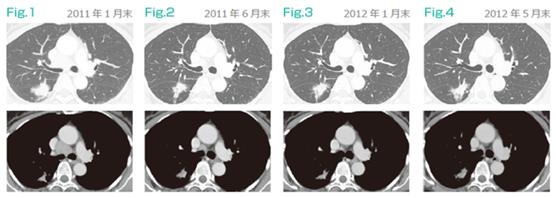

案例:60岁女性 无吸烟史 2011年1月诊断为T4N3M1a肺腺癌(肺内及锁骨上淋巴结转移)。2011年3月初开始CDDP+PEM+BV化疗,并切除了右锁骨上淋巴结,将切除淋巴结溶解制作DC疫苗,以待后用。至6月,CDDP+PEM+BV治疗4次,细胞疗法3次,发现肿瘤缩小(PR),随机停止联合化疗,7月开始维持治疗仅使用贝伐+细胞疗法,观察至2015年5月底肿瘤未进展。